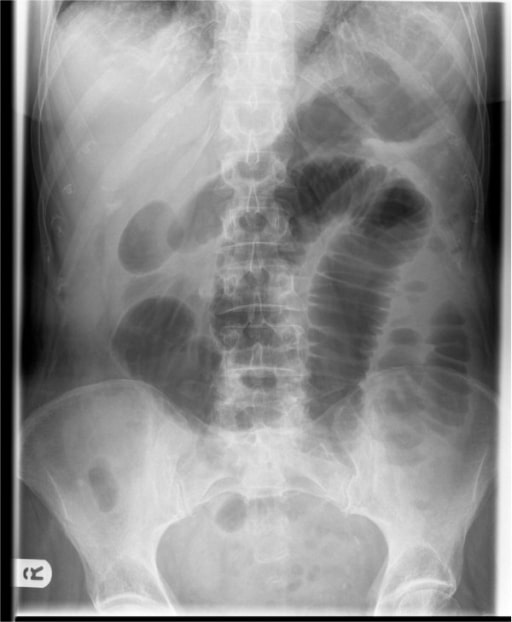

- Abdominal X-ray (best initial test) that would show dilated bowel (screen for free air under the diaphragm)

- CT scan of the abdomen and pelvis with contrast (imaging of choice for diagnosis of LBO) to distinguish between a partial or complete obstruction